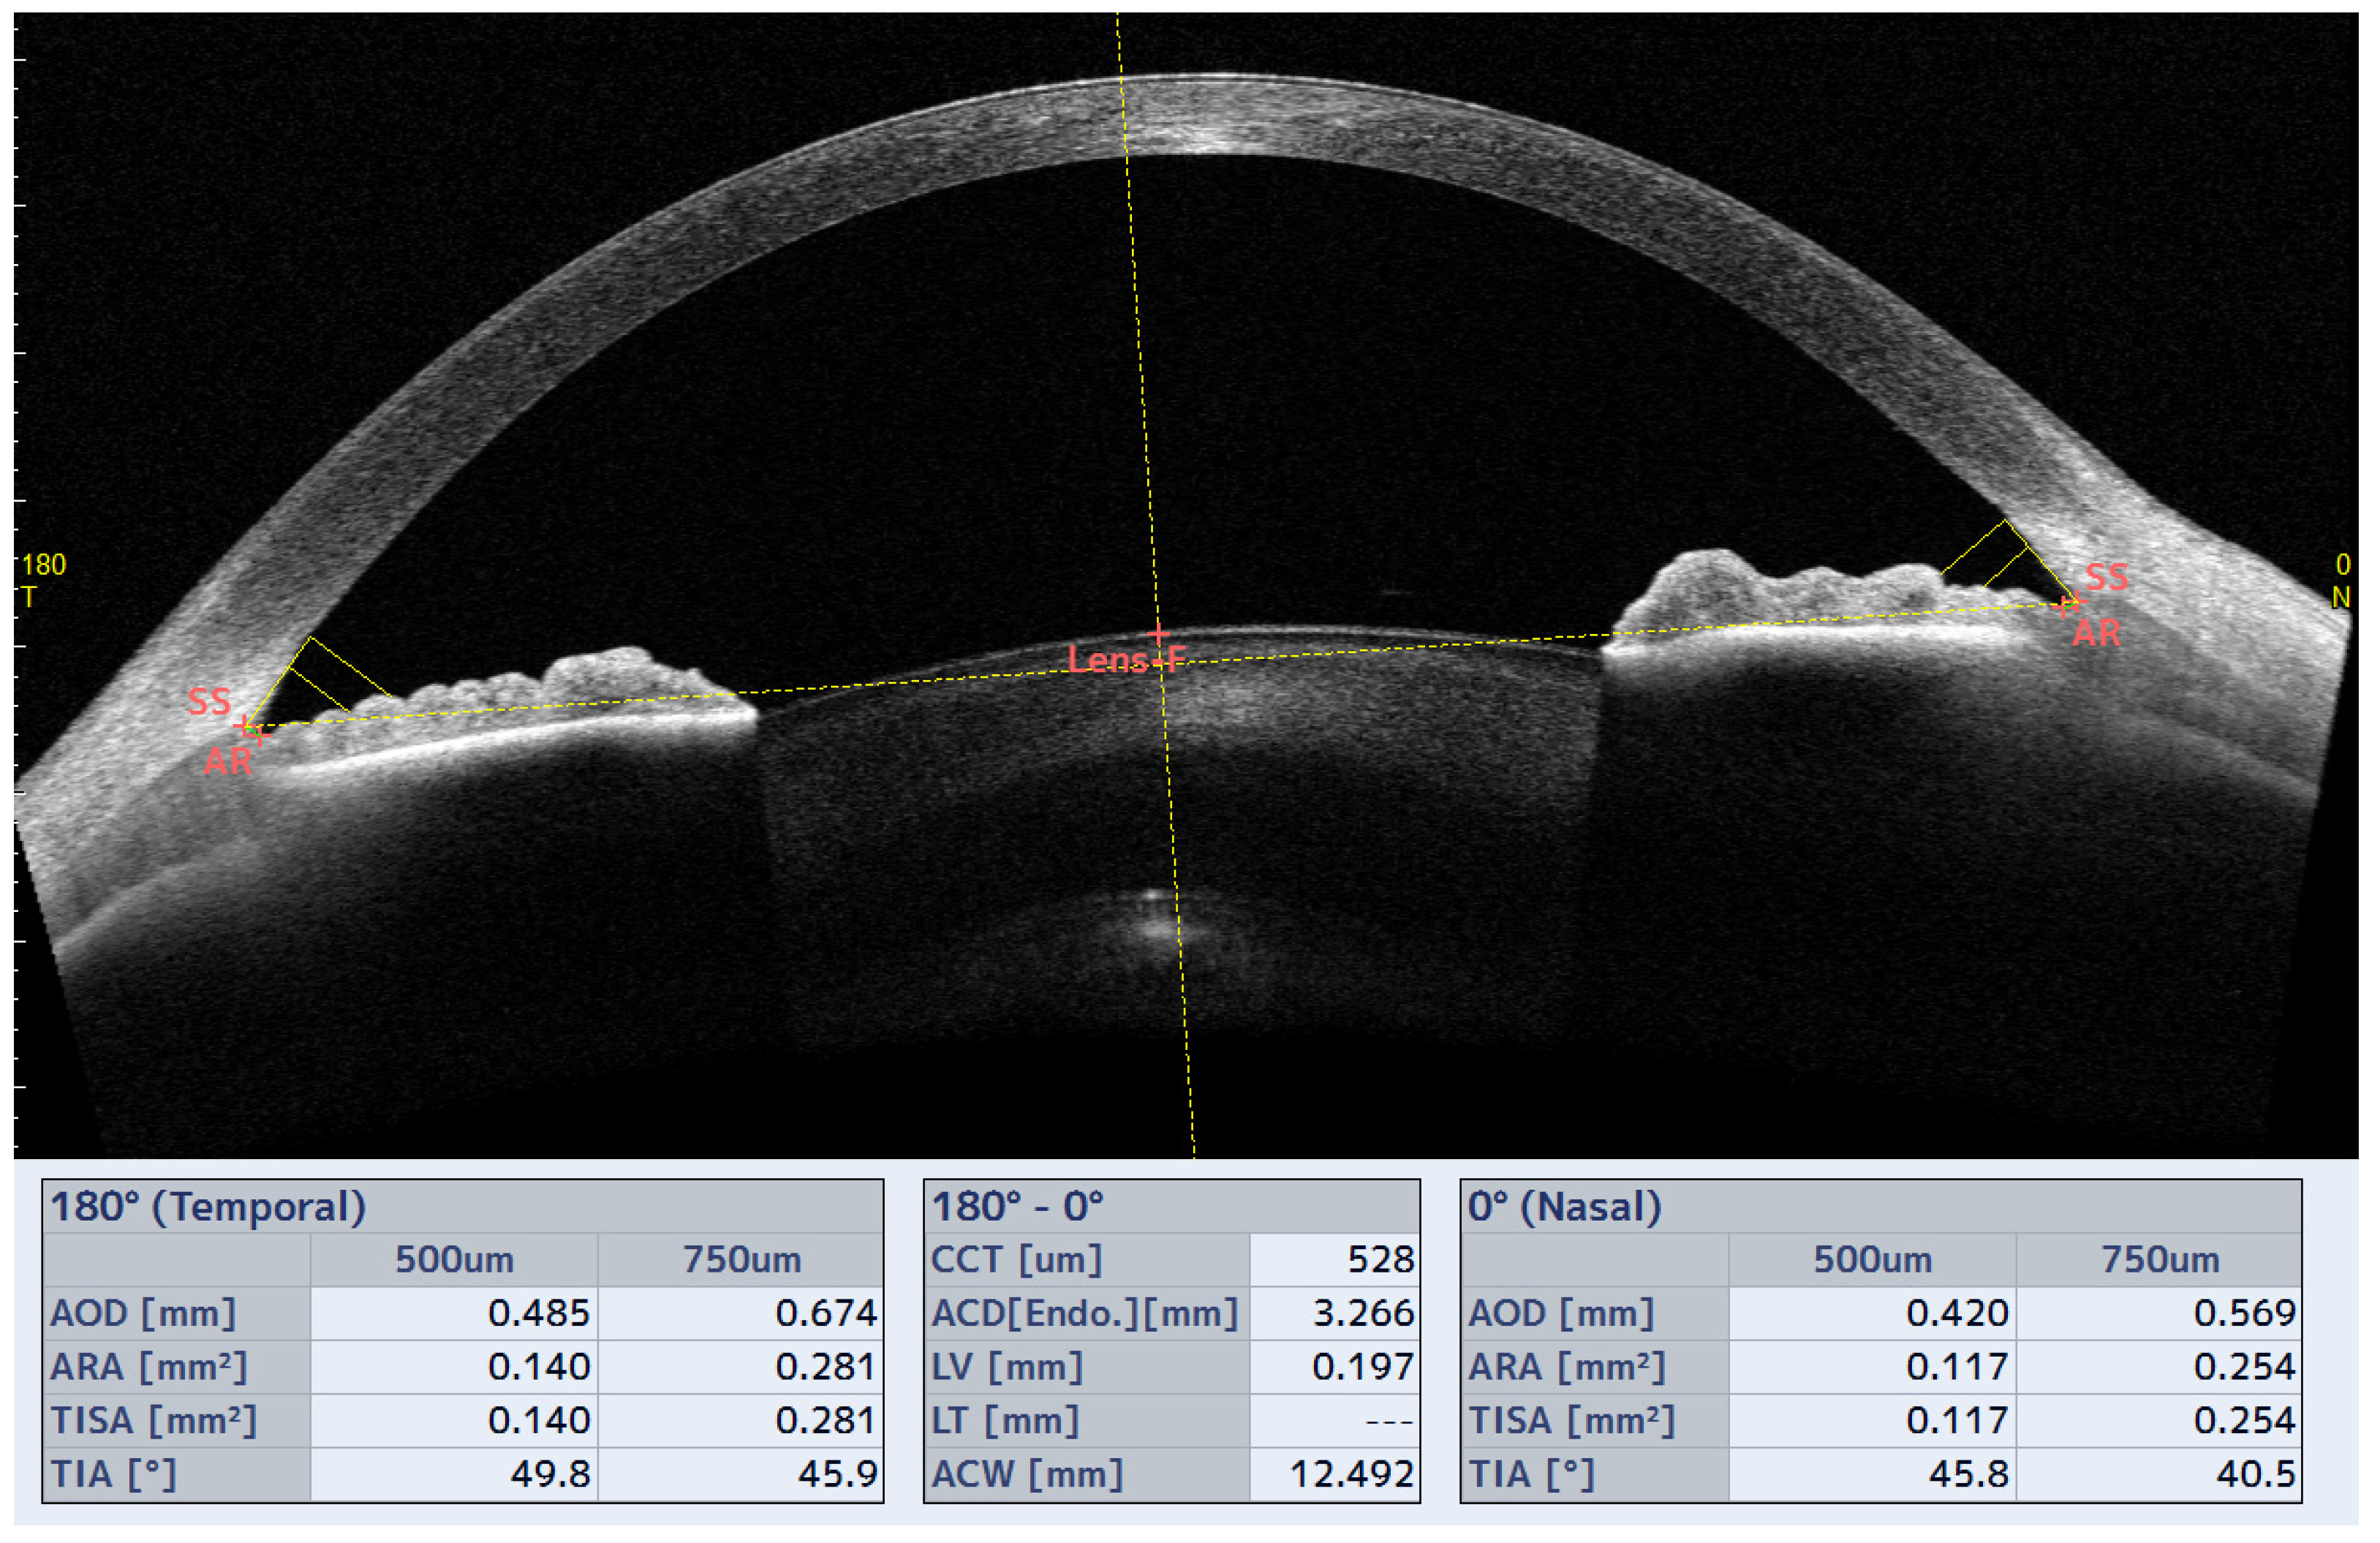

3.4. Iridocorneal Angle and Schlemm’s Canal Parameters

| Before Lens (Mean ± SD) | After Lens (Mean ± SD) | Δ (Mean ± SD) | p | ||

|---|---|---|---|---|---|

| ICA parameters | |||||

| TIA500 0–180° (°) | L1 | 47.55 ± 14.19 | 44.80 ± 12.14 | −2.72 ± 5.33 | 0.01 * |

| L2 | 47.90 ± 13.74 | 46.43 ± 14.17 | −1.54 ± 4.86 | 0.09 | |

| TIA500 90–270° (°) | L1 | 46.71 ± 12.76 | 44.10 ± 12.50 | −2.30 ± 5.26 | 0.02 * |

| L2 | 46.46 ± 12.75 | 44.86 ± 12.59 | −1.60 ± 5.24 | 0.11 | |

| TISA500 0–180° (mm2) | L1 | 0.21 ± 0.08 | 0.20 ± 0.08 | −0.02 ± 0.04 | 0.01 * |

| L2 | 0.21 ± 0.08 | 0.20 ± 0.08 | −0.01 ± 0.03 | 0.38 | |

| TISA500 90–270° (mm2) | L1 | 0.20 ± 0.08 | 0.19 ± 0.07 | −0.01 ± 0.03 | 0.06 |

| L2 | 0.20 ± 0.07 | 0.19 ± 0.07 | 0.00 ± 0.04 | 0.43 | |

| AOD500 0–180° (mm) | L1 | 0.61 ± 0.24 | 0.53 ± 0.24 | −0.08 ± 0.12 | <0.01 * |

| L2 | 0.59 ± 0.24 | 0.56 ± 0.24 | −0.03 ± 0.11 | 0.14 | |

| AOD500 90–270° (mm) | L1 | 0.56 ± 0.23 | 0.49 ± 0.22 | −0.07 ± 0.12 | 0.00 * |

| L2 | 0.53 ± 0.18 | 0.52 ± 0.19 | −0.01 ± 0.10 | 0.72 | |

| ARA500 0–180° (mm2) | L1 | 0.23 ± 0.09 | 0.22 ± 0.09 | −0.02 ± 0.05 | 0.04 * |

| L2 | 0.22 ± 0.09 | 0.22 ± 0.08 | −0.01 ± 0.04 | 0.47 | |

| ARA500 90–270° (mm2) | L1 | 0.21 ± 0.08 | 0.20 ± 0.08 | −0.01 ± 0.04 | 0.09 |

| L2 | 0.21 ± 0.07 | 0.21 ± 0.07 | −0.01 ± 0.04 | 0.61 | |

| ITC index (%) | L1 | 3.26 ± 9.00 | 4.53 ± 12.08 | 1.28 ± 4.53 | 0.19 |

| L2 | 2.62 ± 7.92 | 4.03 ± 9.83 | 1.52 ± 7.99 | 0.15 | |